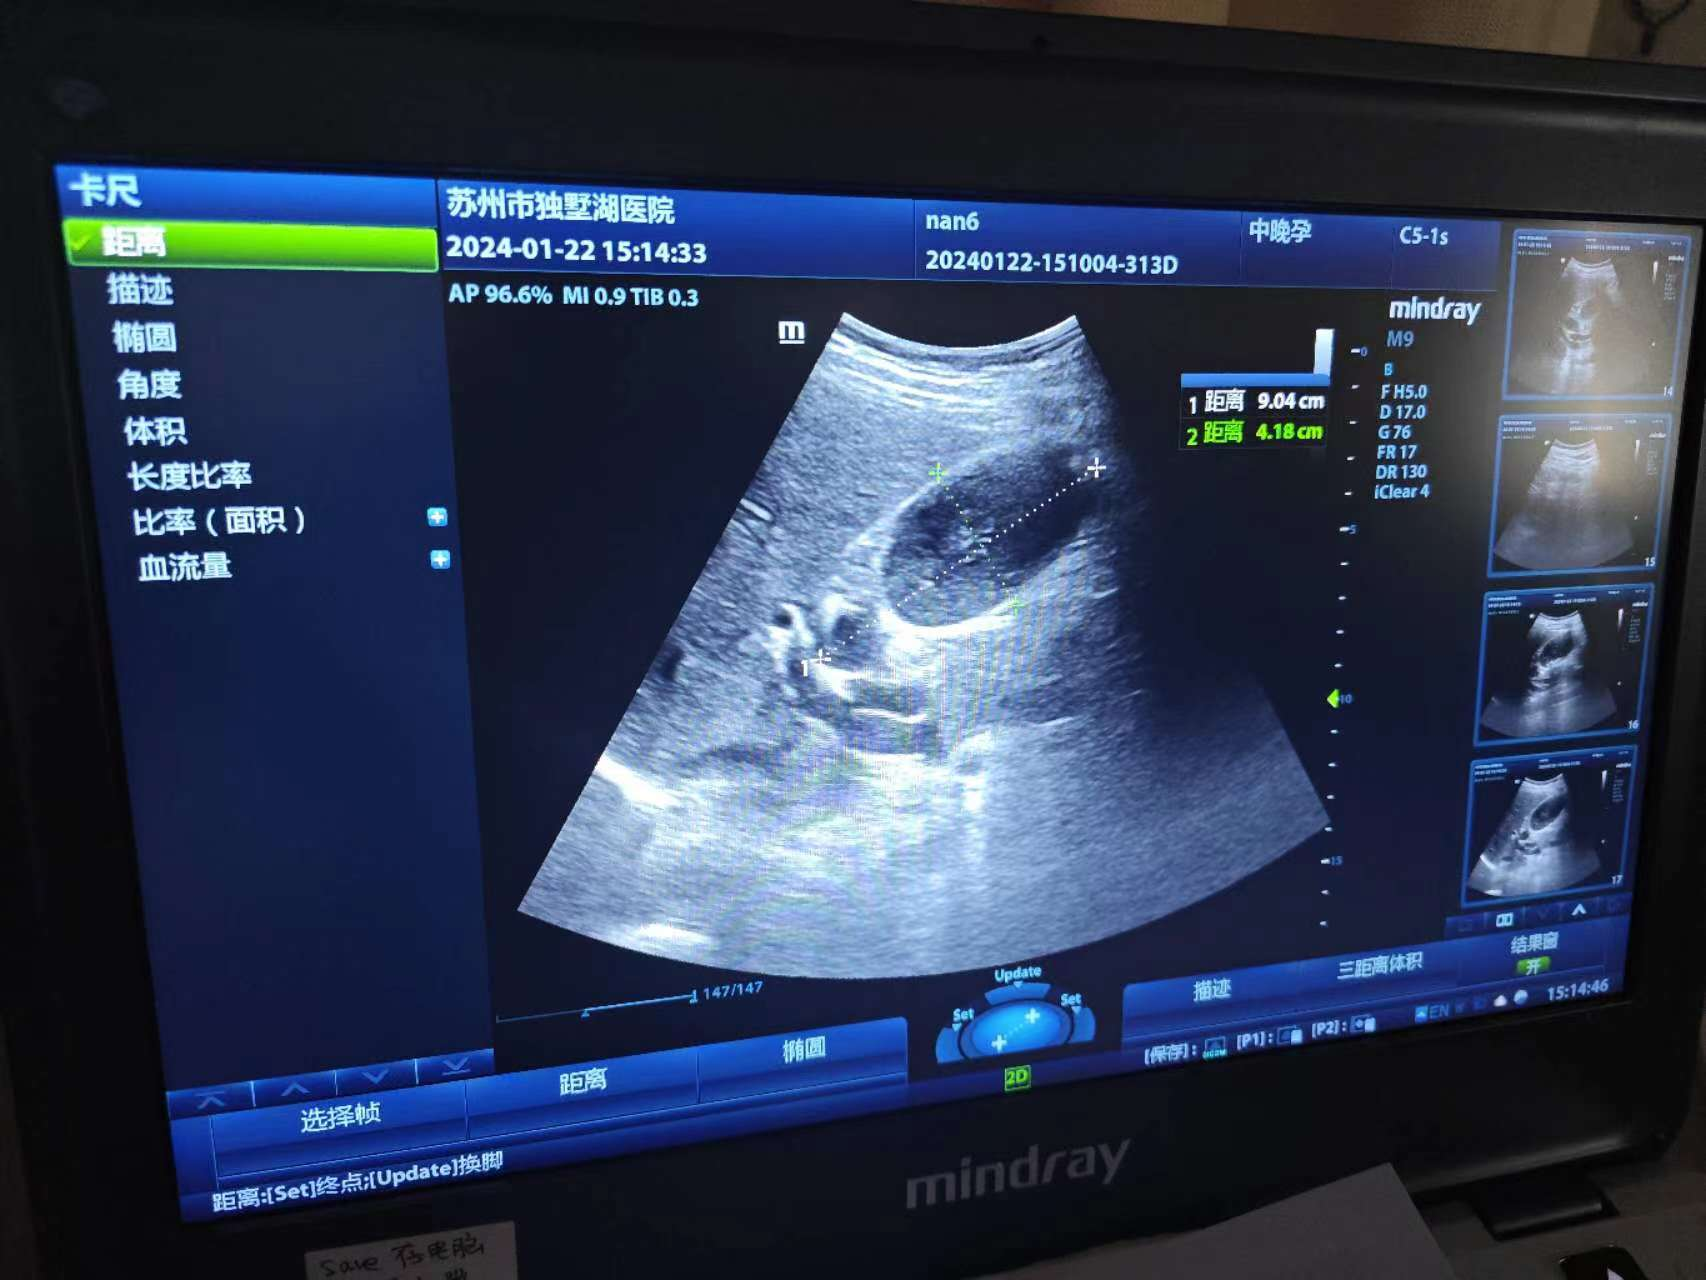

考虑到孕晚期的因素,微创手术难度更大,于是术前再次给小敏复查了胆囊B超,评估胆囊张力、探查胆管。第一阶段的剖宫产手术由妇产科张跃明主任主刀,姜飞洲副主任医师协助,在高超的技巧及精确、迅速的手法下,手术半小时完成,前鞘层、皮下脂肪层加固缝合,为第二阶段手术打下牢固基础。第二阶段手术由普外科杨泽利副主任医师主刀,行低气腹压下腹腔镜胆囊切除术。术中谨慎操作、减少出血,减轻对子宫的刺激,肿大的胆囊迅速被切除并送病理检查。整个手术过程中,由麻醉科李健主任团队实施精准麻醉,为母婴安全保驾护航;妇产科、普外科默契配合,整场手术衔接有条不紊,保障了孕妈妈和胎儿的安全。